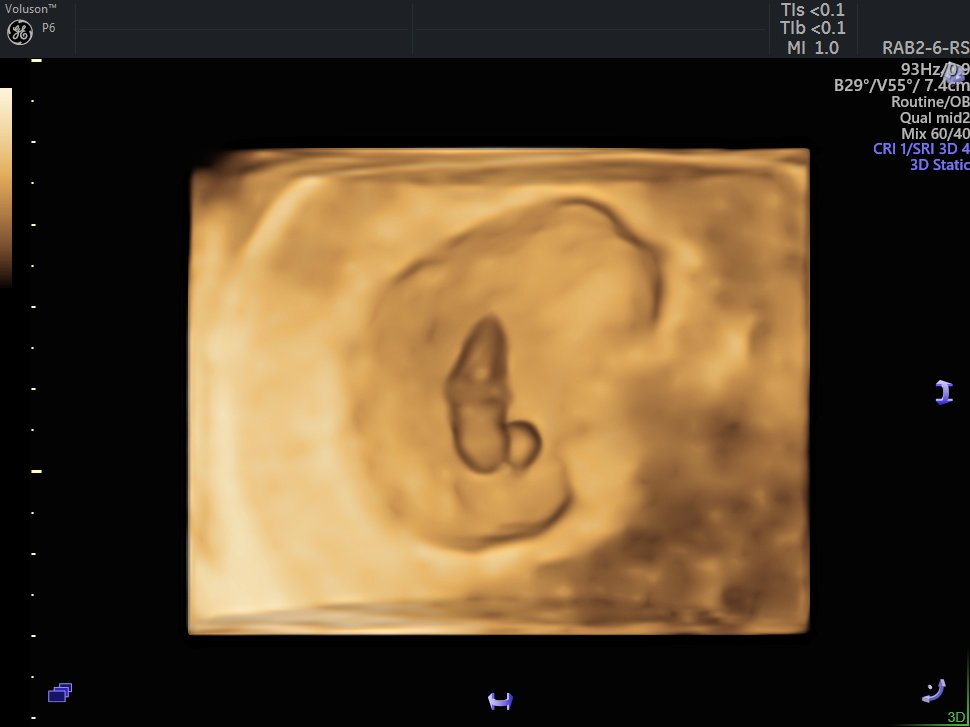

4 D Ultrasonografi

4 Boyutlu (Renkli) Ultrason ve Doppler Ultrasonografi